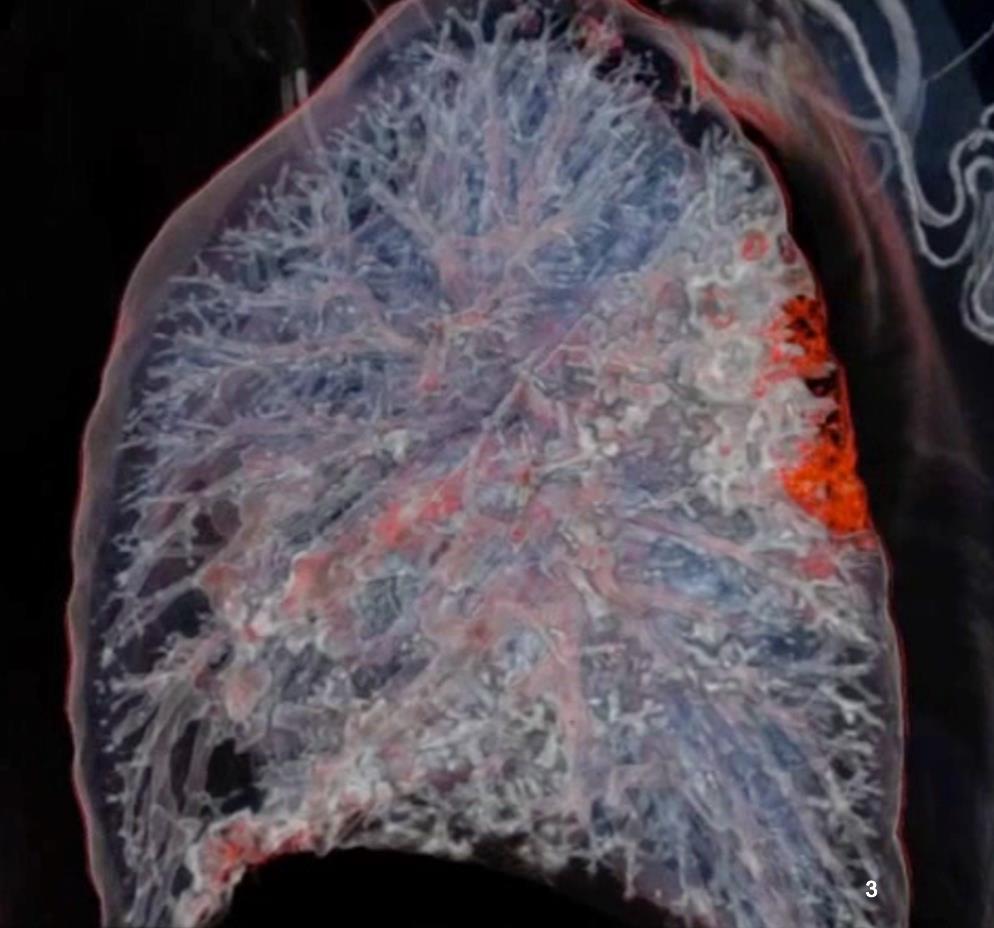

Acute Pediatric COVID-19: CT

21 Imaging of Covid 19 infection in children

3 Phases

Early: "Halo" sign

Local infection

Progressive: Diffuse GGO

Developed: Consolidation

Surr vasc congestion

Inflammation - adj alveoli

Alveoli fill with fluid/cells

• Bilateral & multifocal GGO, +/Consolidations or both

• Halo sign

• Peripheral and subpleural

• Bronchovascular thickening